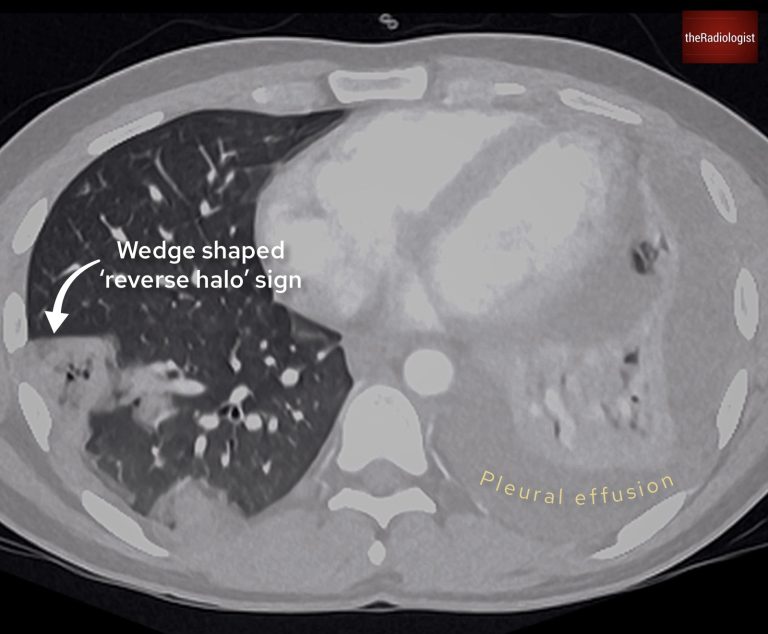

A subsequent CT scan clarified the findings:

• Peripheral, discrete nodules with cavitation.

• Wedge-shaped areas showing a reverse halo sign (atoll sign), where consolidation surrounds ground-glass opacity.

• A new pleural effusion was noted on the left side.

The reverse halo sign is seen in various conditions but is commonly associated with lung infarction, as seen in septic emboli.

At this stage, septic emboli became the leading differential diagnosis. However, identifying the source of infection was critical to confirm and guide treatment.

There is a wedge shaped region of consolidation and groundglass opacity on the right and a pleural effusion on the left.